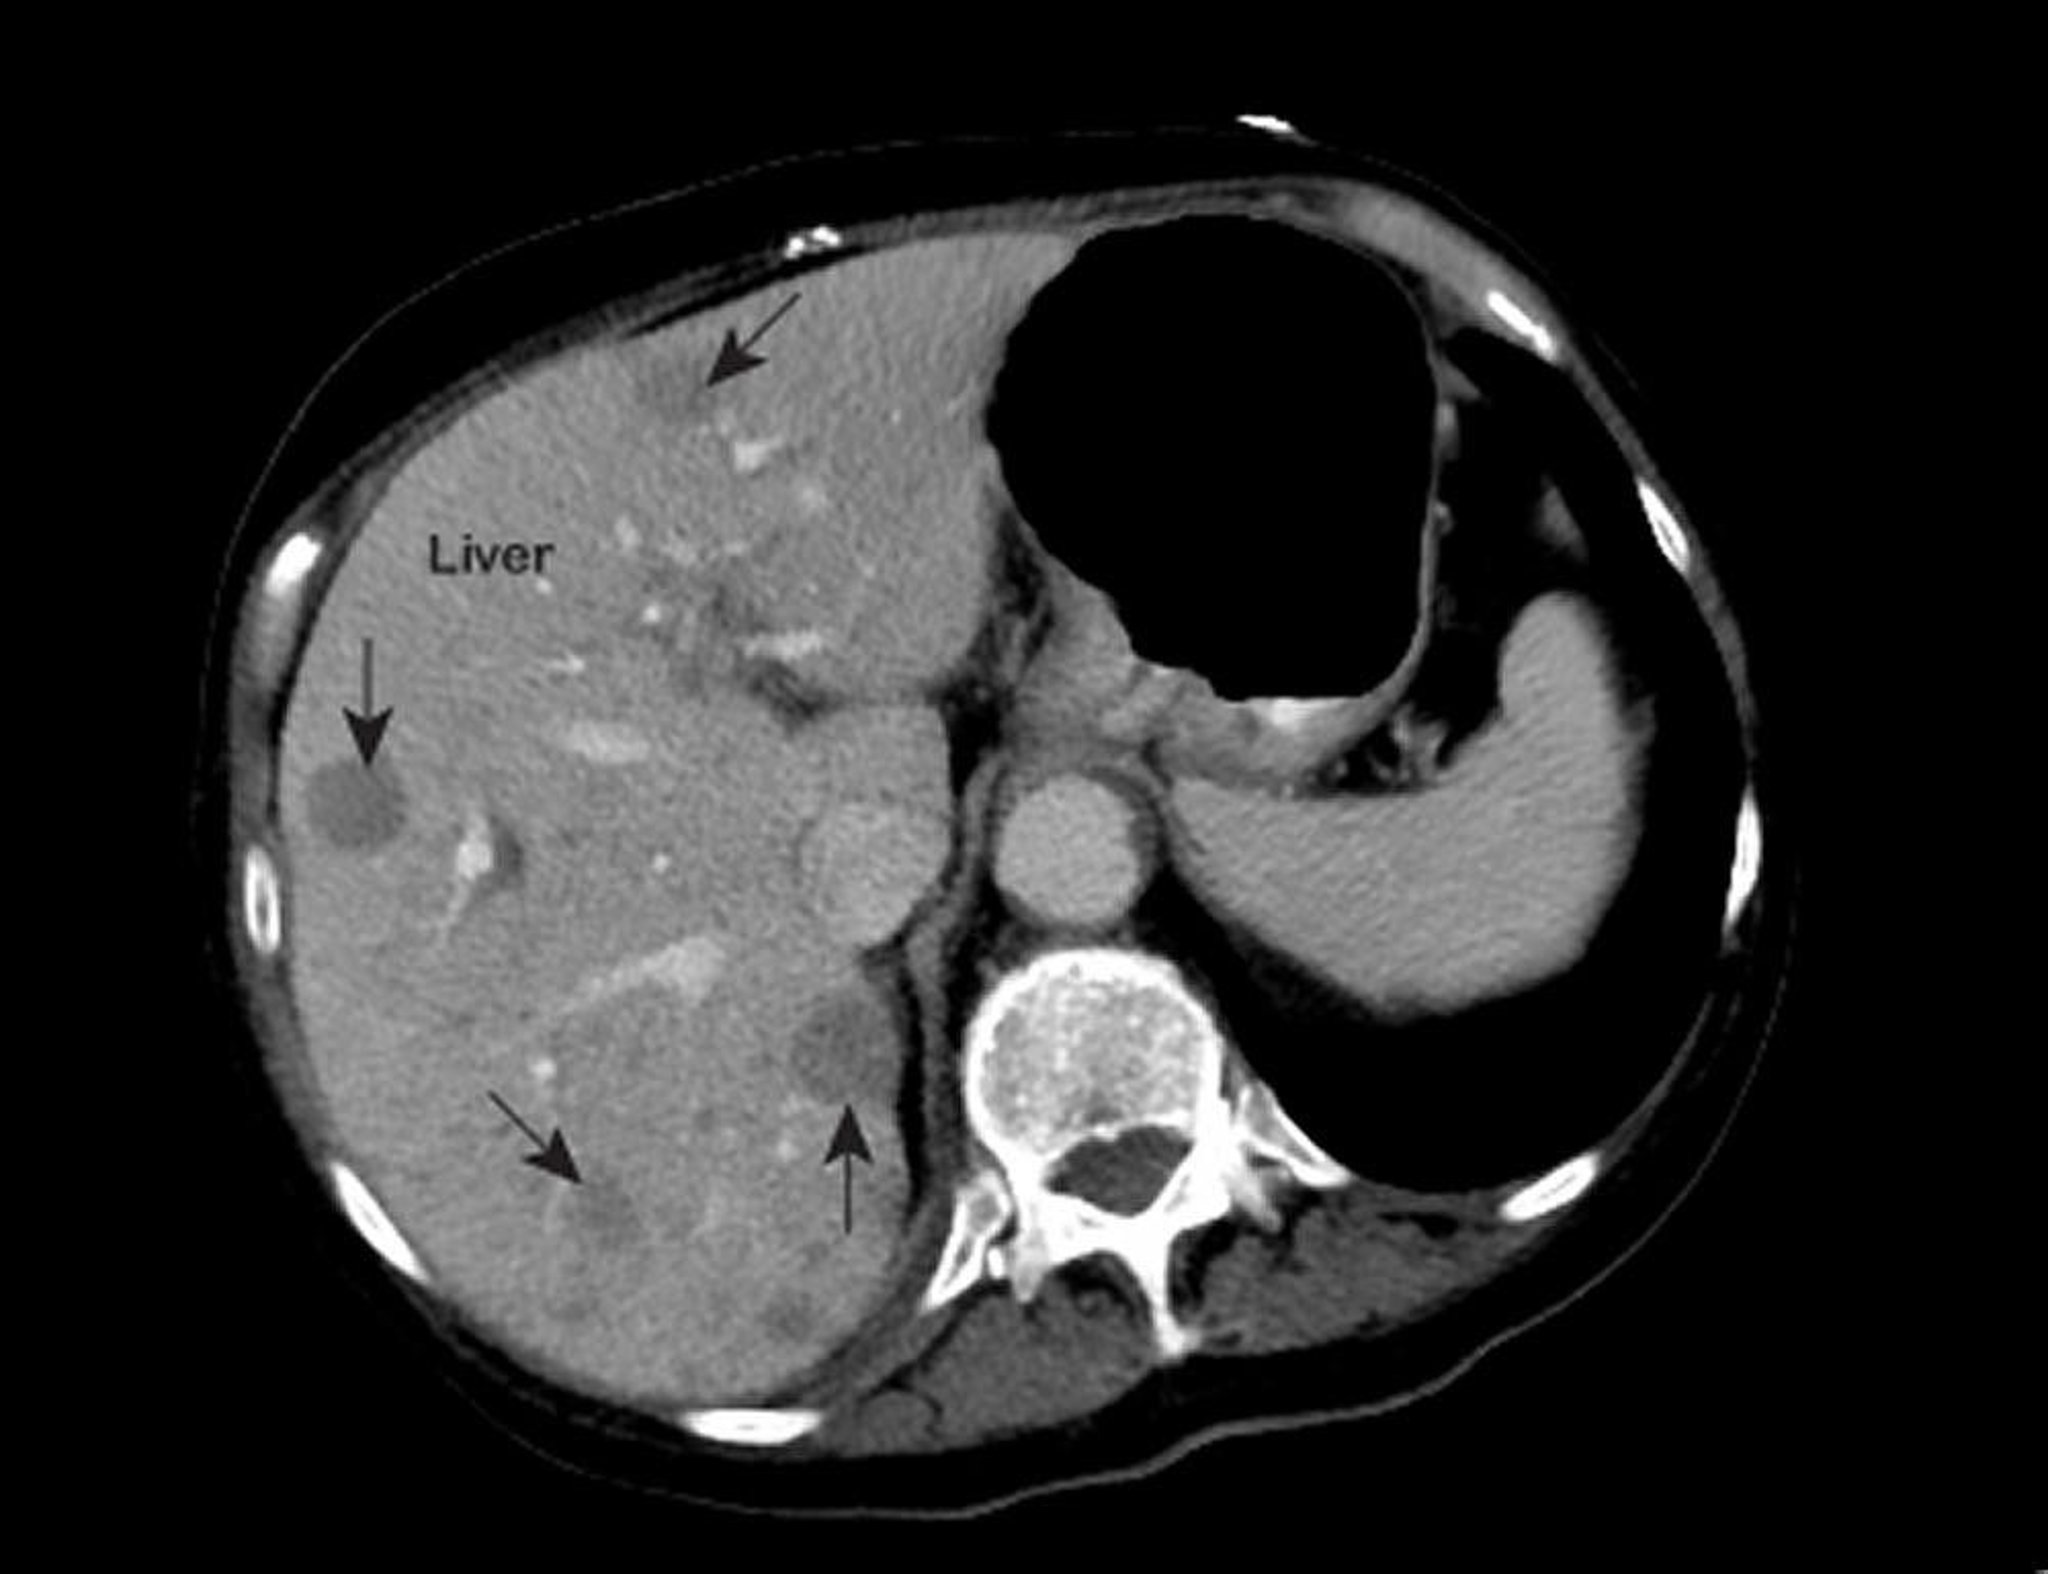

An abnormal magnetic resonance image (MRI) of the chest shows abnormal areas (marked with arrows) inside the liver. These findings are typical of metastatic liver cancer.